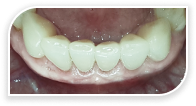

Случай из практики.

Наращивание десны

Часто наши пациенты спрашивают, через какое время после наращивания десна снова опустится вниз. С уверенностью могу сказать, что при соблюдении всех рекомендаций зубы, которые были уже на грани удаления, будут служить пациенту всю жизнь!

Пациентку (Екатерина, 55 лет) в нашу клинику отправили из другой клиники наши коллеги. Цель — вылечить и нарастить десну перед протезированием зубов.

Это был непростой клинический случай с наращиванием десны

в эстетически значимой зоне.

На фотографиях исходное состояние, состояние спустя год после наращивания и 5 лет после наращивания. Результат стабилен.

Десна после наращивания никогда не опустится, если пациент соблюдает все рекомендации врача: приходить на регулярные профилактические осмотры.